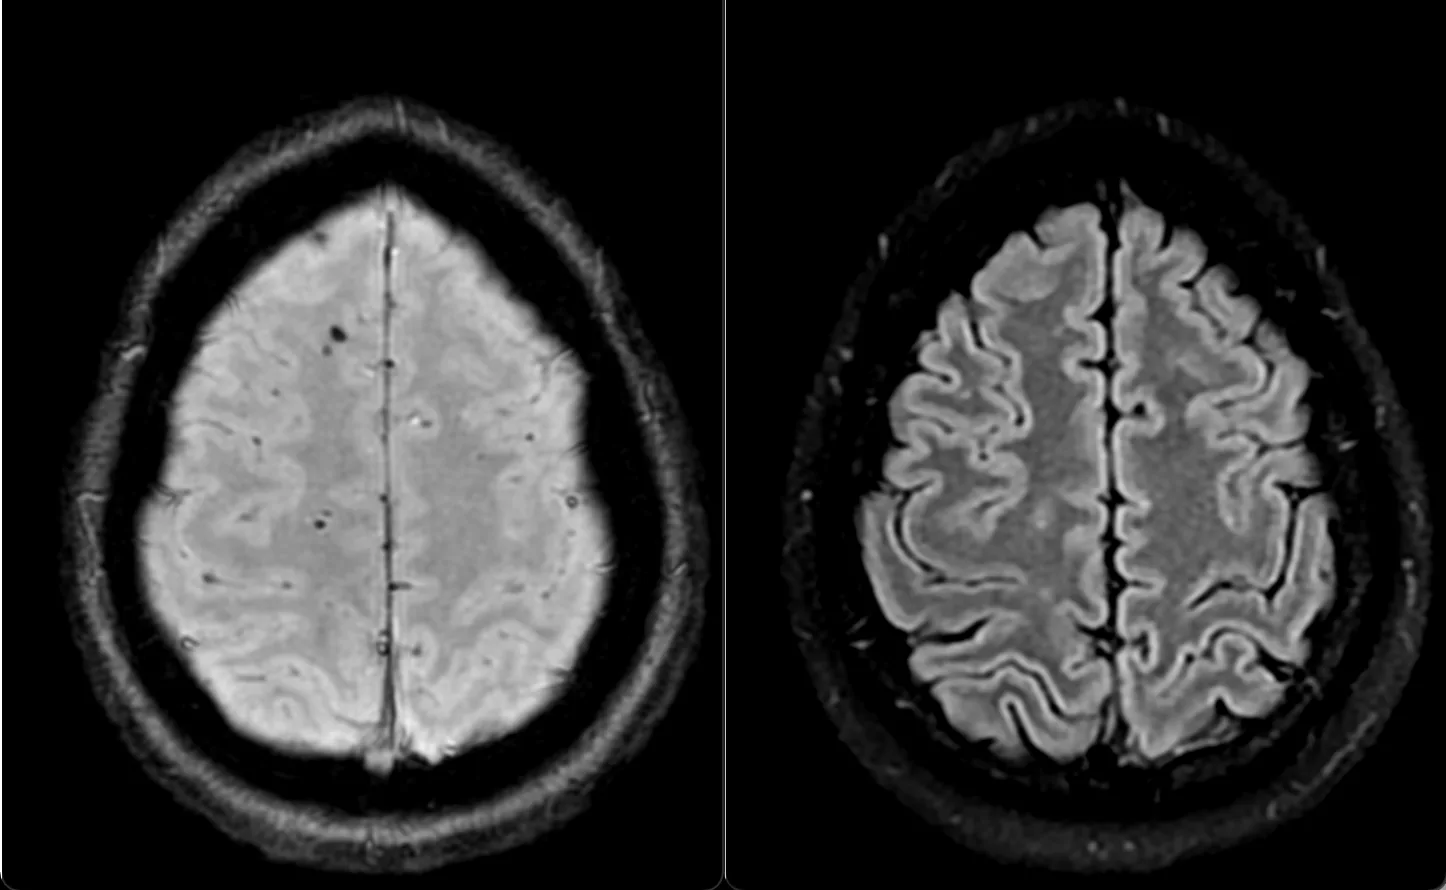

Клинический случай кавернозной мальформации, ассоциированной с венозной аномалией развития (ВАР). Следует напомнить, что ВАР часто сочетаются с каверномами, однако точные статистические данные не привожу, чтобы простимулировать самостоятельный поиск информации и закрепление знаний. Клиническая симптоматика у данного пациента отсутствует, что является типичным сценарием для подобных находок. Диагноз установлен случайно.